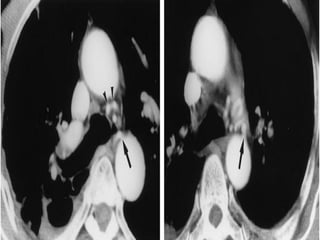

Bronchial artery embolization